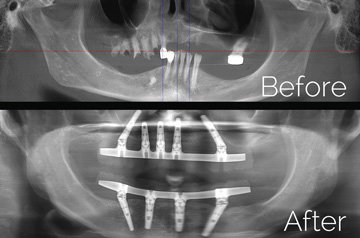

All-on-4 and Teeth-in-a-Day™ Technique

Restorative dentist determines this patient is an exellent candidate for a total all-on-4 implant case; and initiates a referral to the implant surgeon in our Galleria Oral and Maxillofacial Surgery Center, located at Roseville, California.

Surgical solution

- Extractions with Alveoloplasty and Immediate Implants

- Temporary Denture Conversion into Temporary Bridge

- Final Restoration by Restorative Doctor